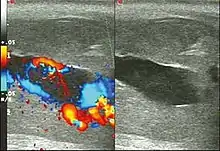

Blood gas testing the blood from the cavernosa of the penis can help in the diagnosis.[3] If the low-flow type of priapism is present, the blood typically has a low pH, while if the high-flow type is present, the pH is typically normal.[3] Color Doppler ultrasound may also help differentiate the two.[3] Testing a person to make sure they do not have a hemoglobinopathy may also be reasonable.[3]

Penile ultrasonography with Doppler is the imaging method of choice, because it is noninvasive, widely available, and highly sensitive. By means of this method, it is possible to diagnose priapism and differentiate between its low- and high-flow forms.[11]

In low-flow (ischemic) priapism the flow in the cavernous arteries is reduced or absent. As the condition progresses, there is an increase in echogenicity of the corpora cavernosa, attributed to tissue edema. Eventually, changes in the echotexture of the corpora cavernosa can be observed due to the fibrotic transformation generated by tissue anoxia.[11]

In high-flow priapism normal or increased, turbulent blood flow in the cavernous arteries is seen. The area surrounding the fistula presents a hypoechoic, irregular lesion in the cavernous tissue.[11]